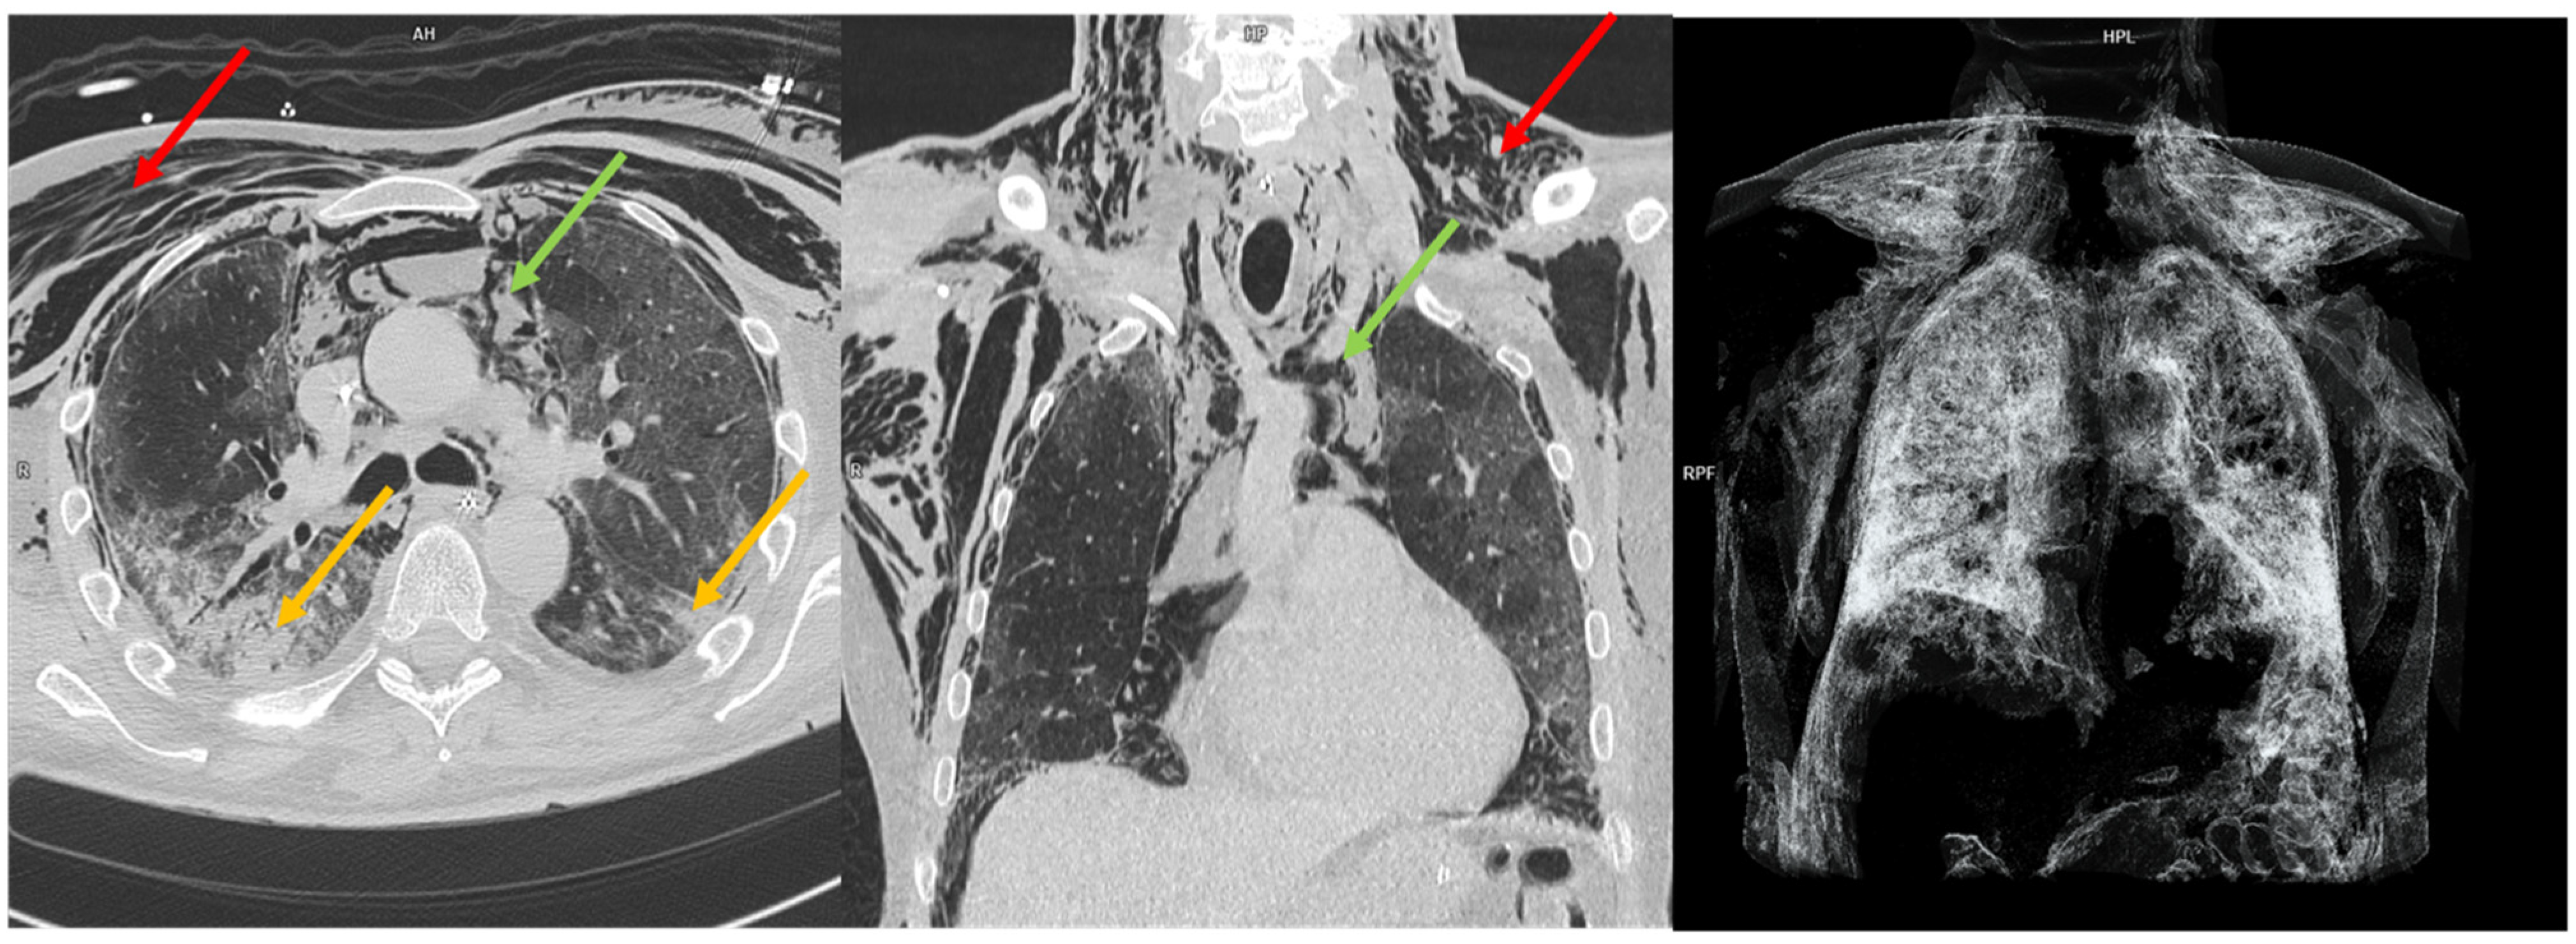

- Paternoster, G.; Belmonte, G.; Scarano, E.; Rotondo, P.; Palumbo, D.; Belletti, A.; Corradi, F.; Bertini, P.; Landoni, G.; Guarracino, F.; et al. Macklin Effect on Baseline Chest CT Scan Accurately Predicts Barotrauma in COVID-19 Patients. Respir. Med. 2022, 197, 106853. [Google Scholar] [CrossRef] [PubMed]

- Belletti, A.; Pallanch, O.; Bonizzoni, M.A.; Guidi, L.; Cobelli, F.D.; Landoni, G.; Zangrillo, A.; Bonis, M.D.; Palumbo, D. Clinical Use of Macklin-like Radiological Sign (Macklin Effect): A Systematic Review. Respir. Med. 2023, 210, 107178. [Google Scholar] [CrossRef] [PubMed]

- Maccarrone, V.; Liou, C.; D’souza, B.; Salvatore, M.M.; Leb, J.; Belletti, A.; Palumbo, D.; Landoni, G.; Capaccione, K.M. The Macklin Effect Closely Correlates with Pneumomediastinum in Acutely Ill Intubated Patients with COVID-19 Infection. Clin. Imaging 2023, 97, 50–54. [Google Scholar] [CrossRef] [PubMed]